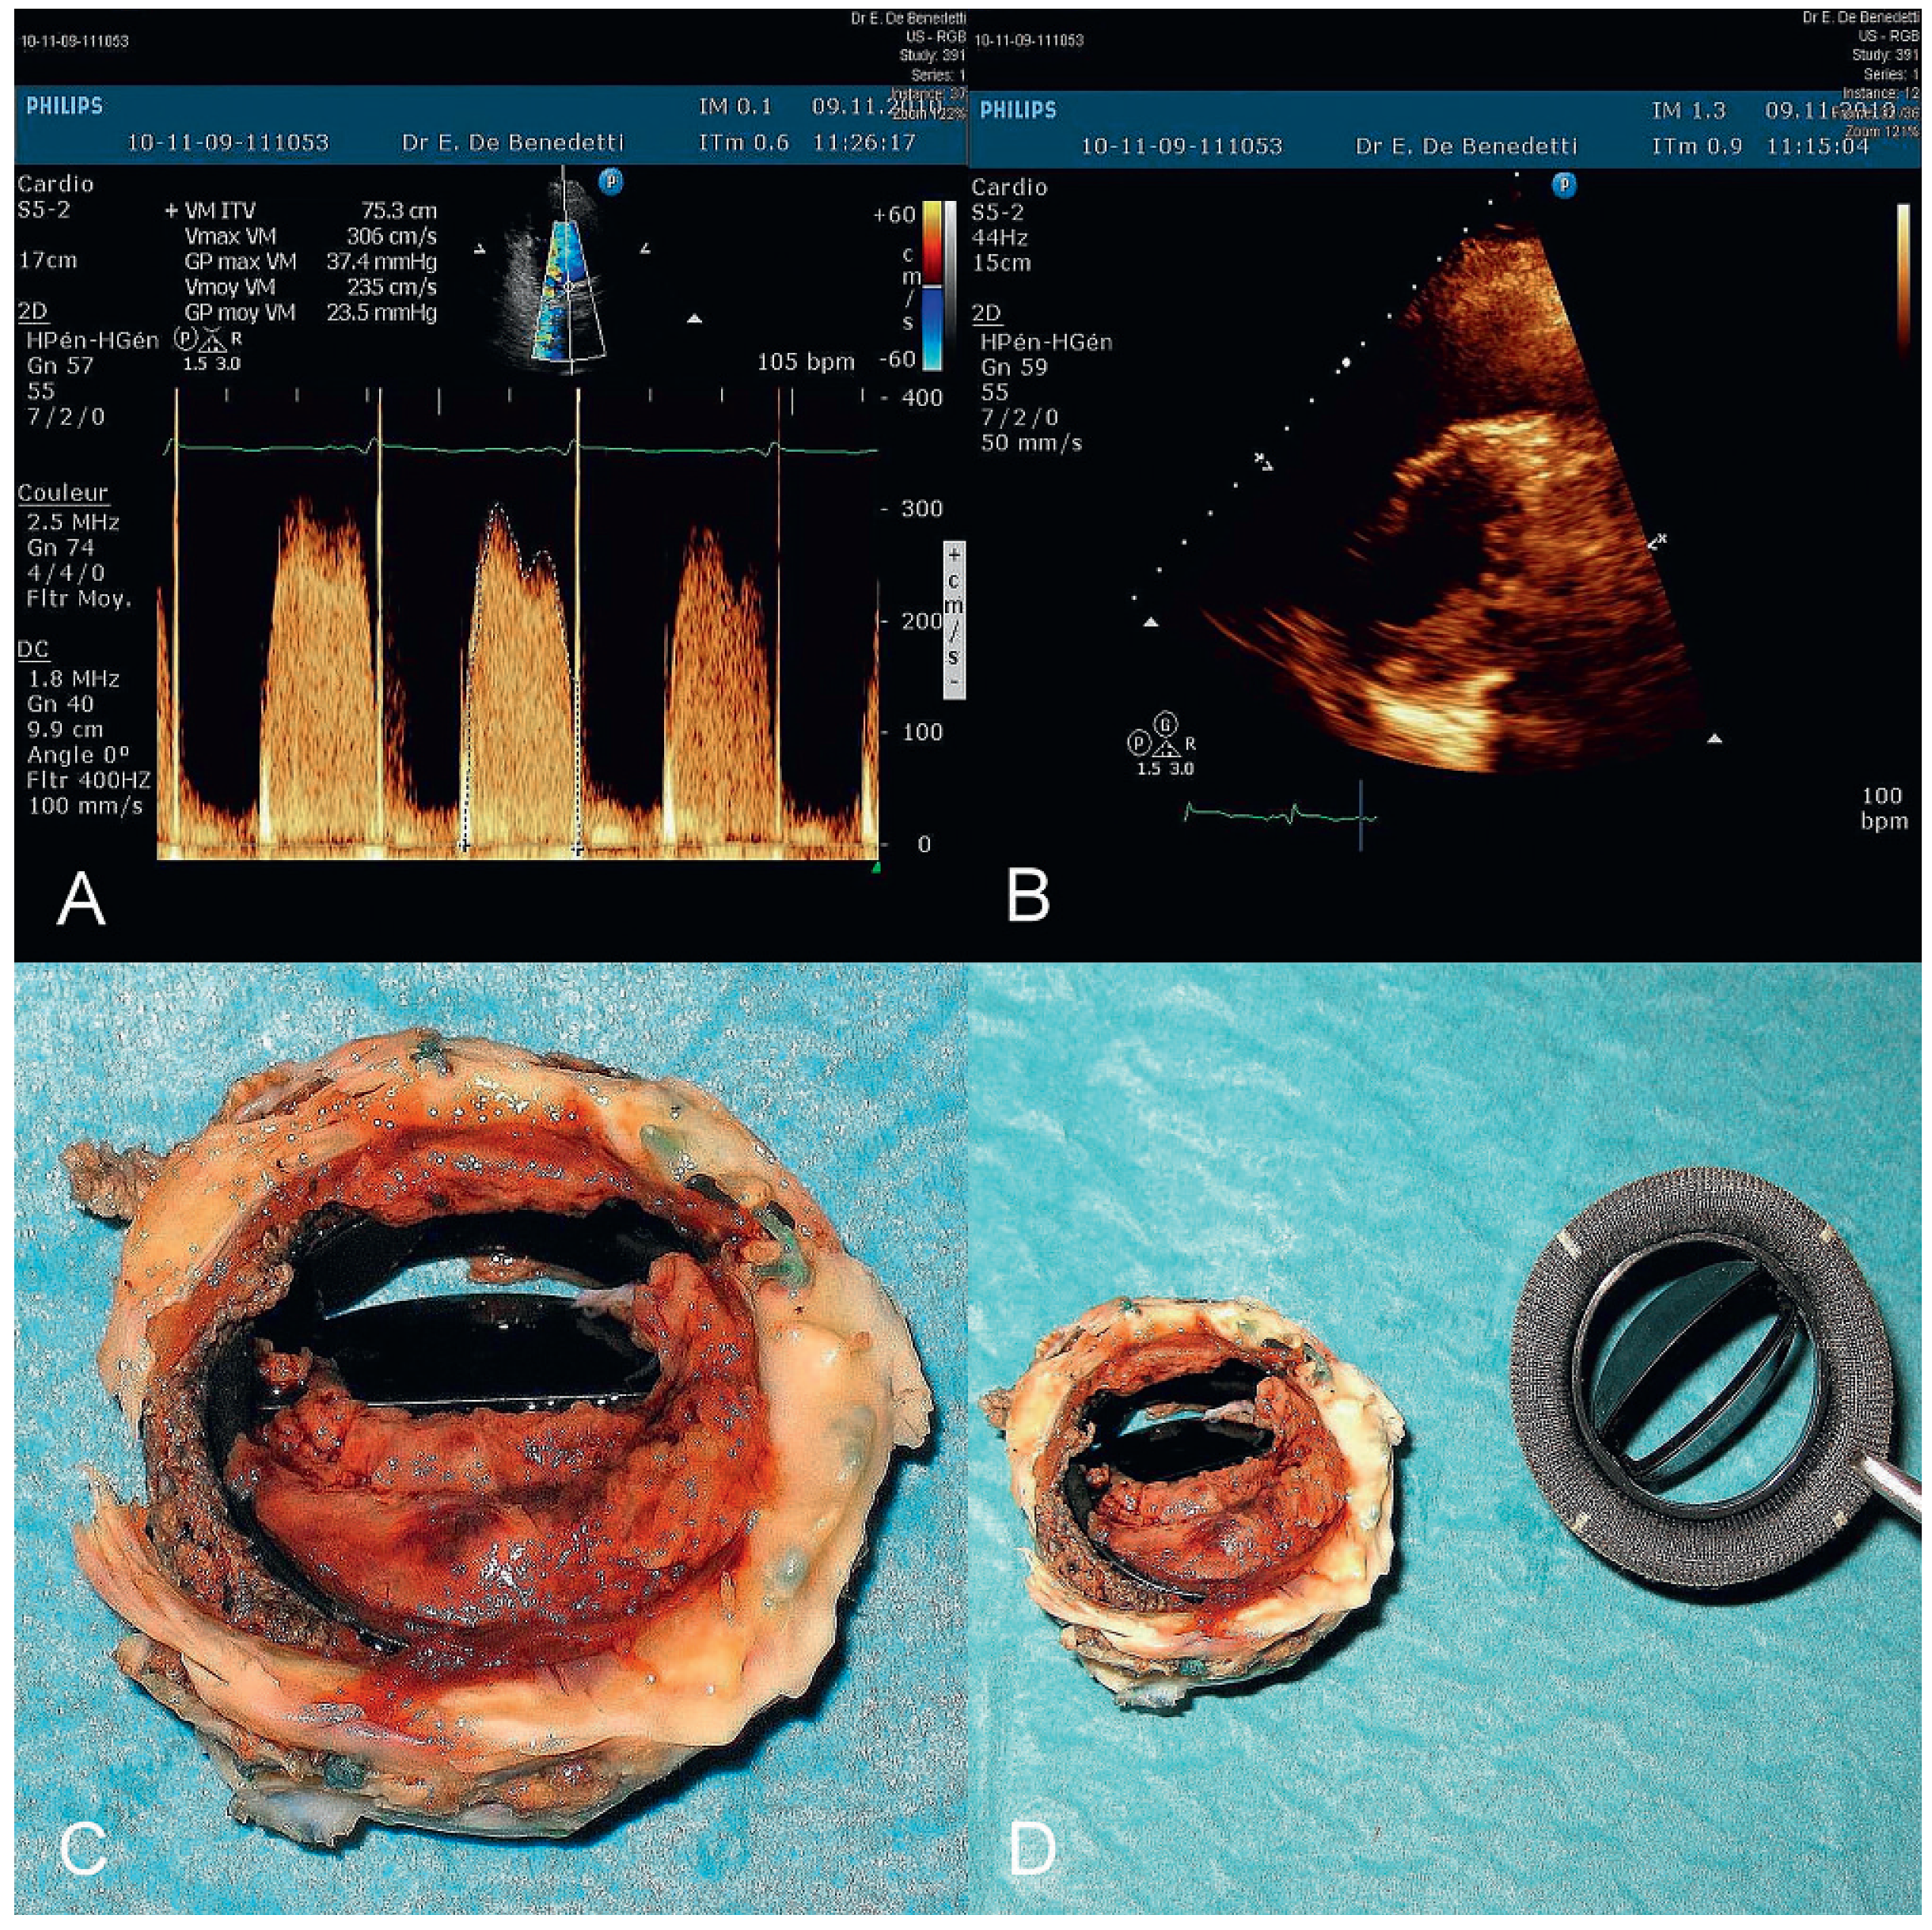

Mechanical Mitral Valve Thrombosis in a 25-Year-Old Man Who Stopped Taking His Acenocoumarol Treatment